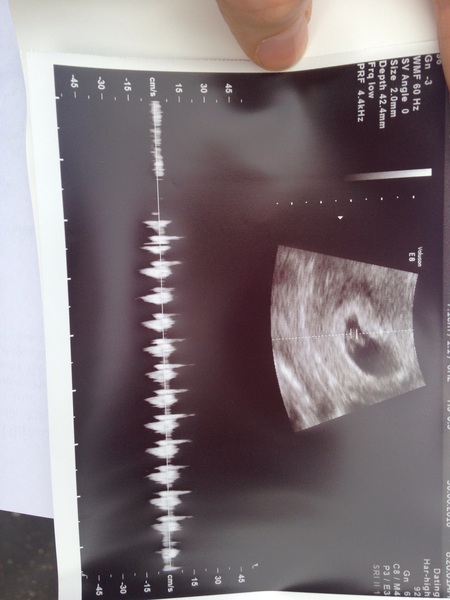

I am 7+1 (although I know I ovulated 3 days late) and on my way to my scan to see if there is a heart beat

OMG wish me luck ConfusedConfusedConfused

A 9 mm bean with a strong heart beat SmileGrinSmile

Ever yay for bean's strong heartbeat! Congrats.

Ever woohoo! So happy your little bean is fine, I bet you're so relieved Smile

ever yay that you have a content little bean! Bet you feel relieved.

Lovely scan ever!!

Ever congrats on the healthy little bean!